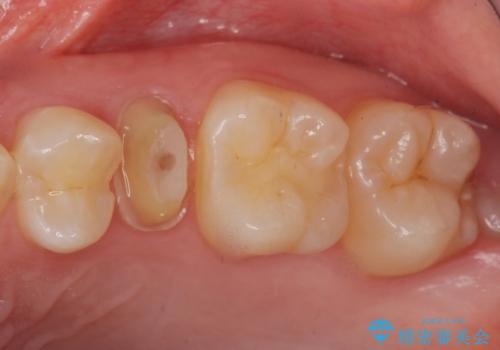

- 以前つけた被せ物がすぐにはずれてしまい1年以上放置してしまったことを主訴に来院された患者様です。

精査したところ、左上の小臼歯(左上5)は被せ物がないまま放置していたことにより、両隣の歯が寄ってきてスペースが少なくなり、また隣の歯(左上4)も虫歯になっていました。

以前つけた被せ物は1週間でとれてしまったそうで、歯ぎしりのご自覚もあることから、咬み合わせの調整を丁寧に行いました。

仮歯およびクラウンの仮付け期間を設け、はずれにくいことや咬み合わせに問題がないことを確認した上で本付けを行いました。

治療終了後、ナイトガードの作製もご希望されました。